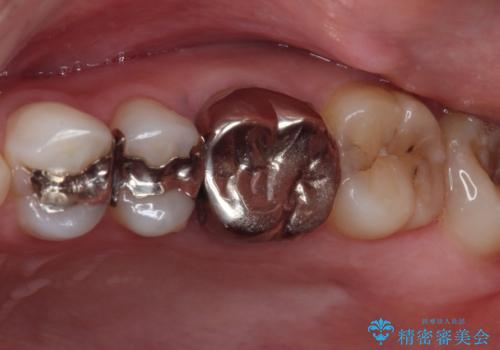

- 奥歯の銀歯が外れたことをきっかけに、全ての銀歯をセラミックに替えたいとのことで来院された患者様です。

第一大臼歯4本と、メタルインレーが装着されている2歯をセラミッククラウンならびにセラミックインレーにて補綴治療・修復治療を行うこととしました。